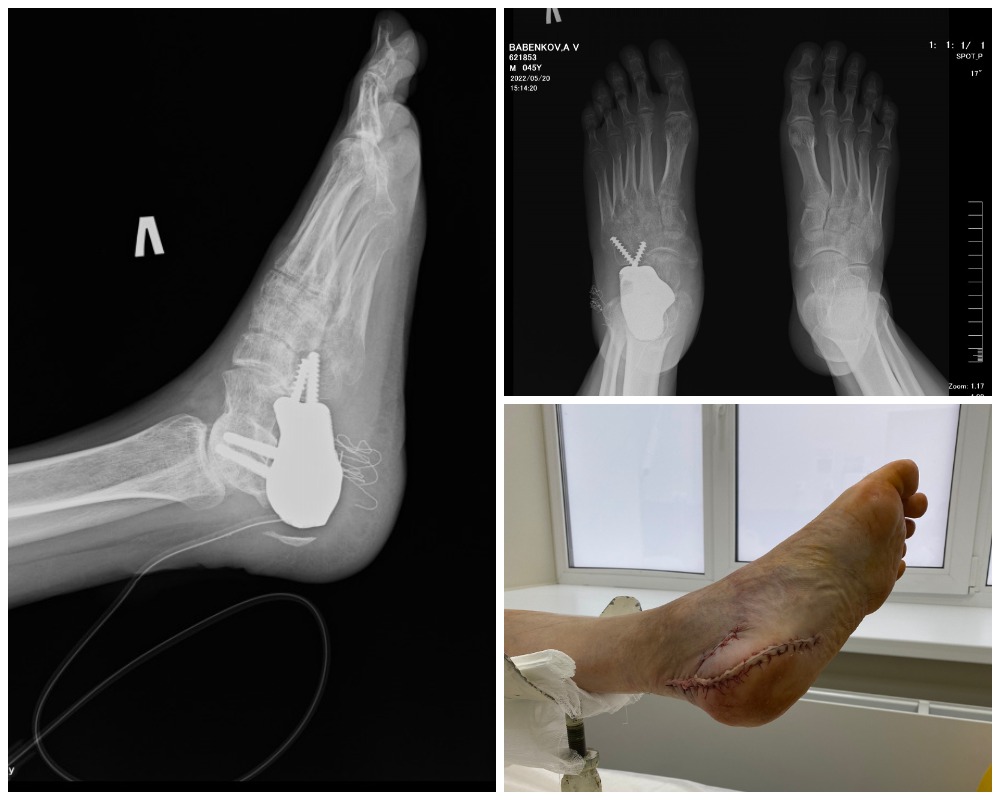

Так выглядит протез пяточной кости на рентгеновском снимке и в жизни сразу после операции

— Наша цель была – радикально удалить опухоль, которая располагалась в кости, выходила в мягкие ткани, выходила в зону сустава, вычленить эту кость с окружающими тканями и заменить ее индивидуальным З-D эндопротезом, — рассказывает Григорий Владимирович Зиновьев.

Благодаря слаженному взаимодействию биоинженеров и врачей российский производитель индивидуальных эндопротезов создал из титана прототип пяточной кости по индивидуальным размерам.